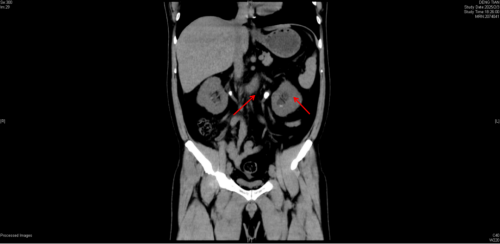

术前CT片显示双侧肾结石、双输尿管结石导致双肾积水

术后复查,双侧输尿管支架管留置,梗阻解除